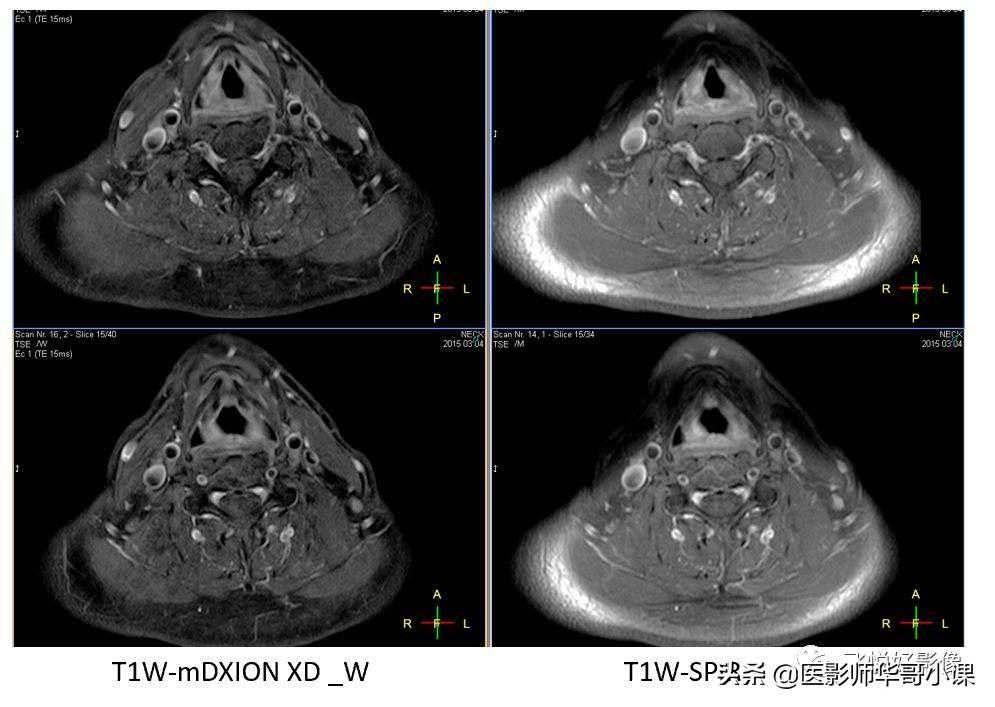

一次成像,四种组织对比度

在颈部扫描中,脂肪抑制一直是难点,上图中右侧一组图像是T1W_SPIR,看到脂肪抑制不均匀,仍残留部分脂肪信号。左侧一组图像是mDIXON_XDTSE,脂肪抑制均匀,更好的显示组织对比。

在颈椎扫描中,使用三种脂肪抑制技术进行成像,SPIR脂肪抑制不均匀,STIR脂肪抑制均匀,但SNR较低,mDIXON既能均匀抑制,也能保留良好的SNR。